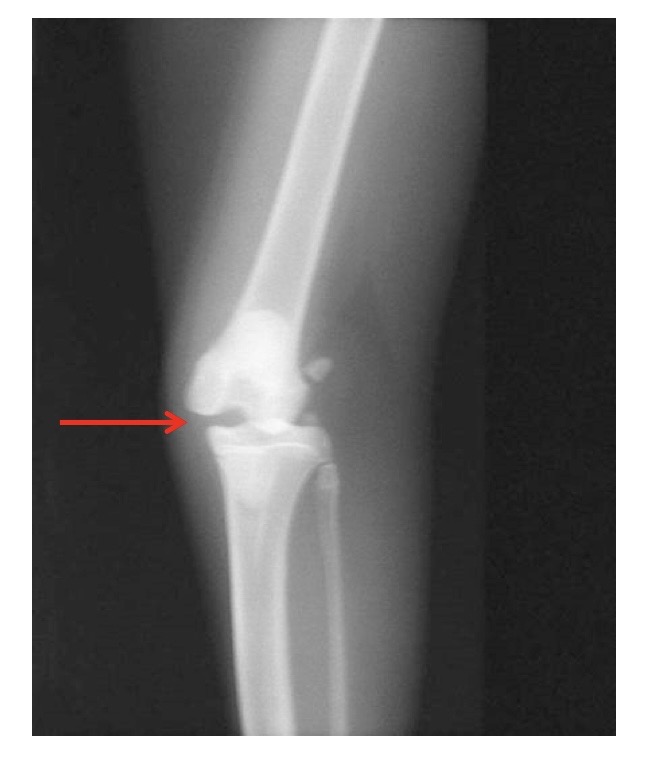

what is this showing?

valgus stress applied to joint → MCL injury